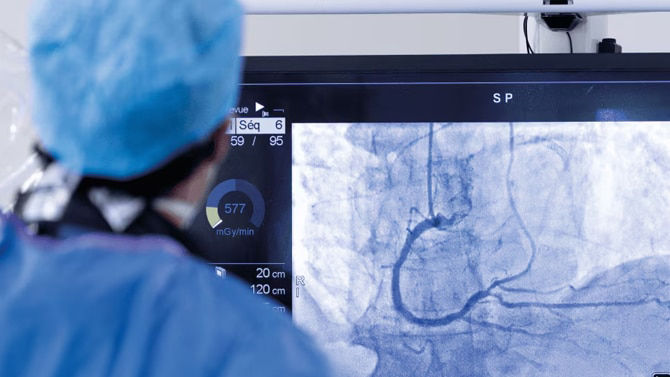

Upgrades tailored for your specific system

Enhance image quality with AI-powered software. Optimize productivity and operations with one holistic view. Extend your system's capabilities and lifespan with innovative options. Reap the benefits captured below and more.